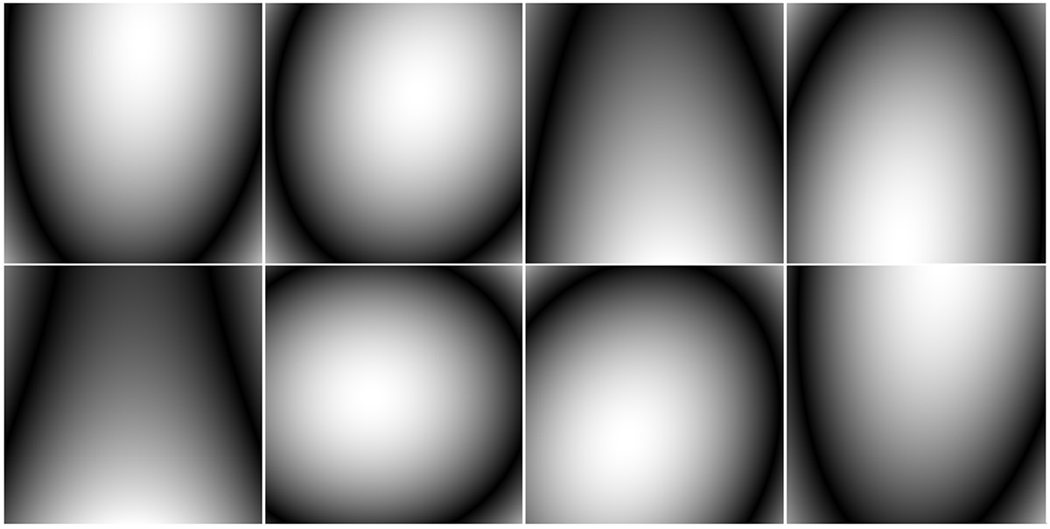

A (256256) brain image was used to compare the performance of noiselet encoding and Fourier encoding in MCS-MRI for different acceleration factors. Eight complex sensitivity maps (Fig. 7) obtained from the head coil of a Siemens Skyra 3T scanner were used to perform the simulations. For solving the minimization program in (10), we used the nonlinear conjugate gradient with the backtracking line search method [7]. The measurement matrix () was the discrete Fourier transform matrix while the daubechies-4 wavelet transform matrix () and TV were used as sparsifying transforms.